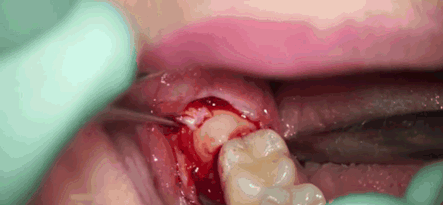

主要是智齿它位置不正

如果位置越深

离神经越近

就越可能会影响到下牙槽神经

拔上颌智齿的时候还不存在这个问题

毕竟上颌的神经是上牙槽后神经

敏感度较低

但是下颌智齿就不一样了

下牙槽神经是感觉神经

一旦出现损伤

下颌牙齿、下唇的感觉都会减弱